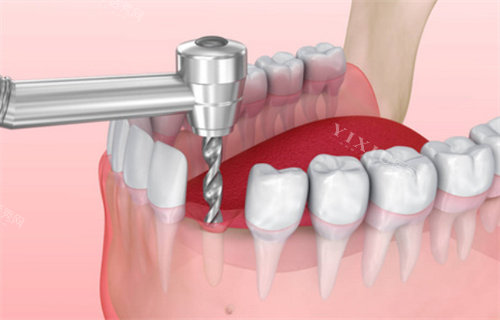

天悦口腔采用的智能化种植技术,通过CBCT比较准扫描、3D模拟种植方案设计,实现小创口不痛种植体验。国产创英种植体作为主打产品,其四级纯钛材质与骨结合性能优异,5年临床使用成功概率高达98.2%,与韩国登腾种植体97.6%的成功概率相当,但价格更为亲民。

针对骨量不足患者,天悦口腔提供多种骨增量解决方案,包括引导骨再生术(价格3000元起)、上颌窦提升术(价格4500元起)等辅助项目,确保种植体长期稳定性。术后提供长期免费复查服务,这在东莞地区属于较为完善的服务支持体系。